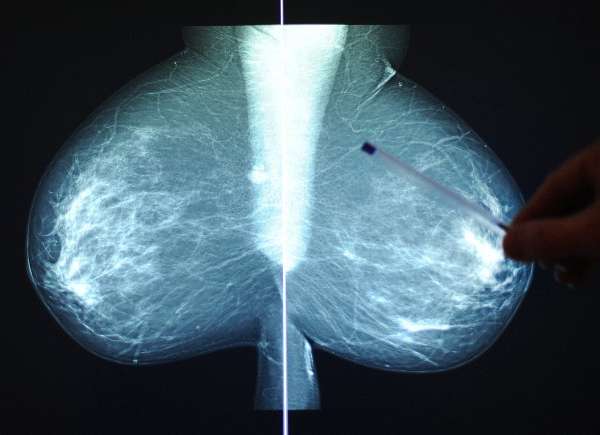

Eine chinesische Studie untersuchte den Einfluss der Arbeitszeiten auf das Krebsrisiko bei Frauen. Ihr Ergebnis: Besonders Frauen, die nachts